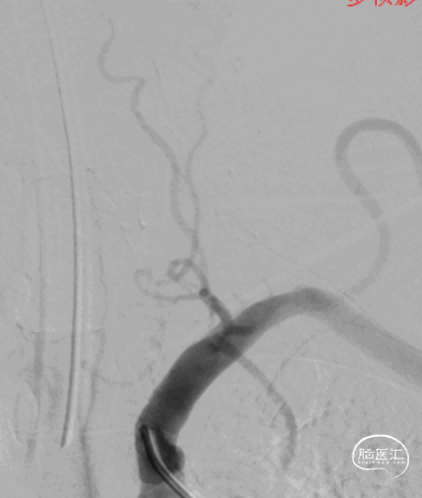

图8. 开通失败后造影

综合术前辅助检查,(Core+pen)/Core=3.58;Pen>15ml;Core<70ml(图3);发病时间小于24小时,存在取栓指征,但是当地医院手术经验告诉我们左侧椎动脉慢性闭塞,且开通异常困难,常规手术方案很难成行,术前制定合理且可行的手术方案至关重要。方案1:仍采用左侧椎动脉+基底动脉取栓的正向开通方案,可能会继续浪费大量时间,甚至最后以失败告终。方案2:采用右侧椎动脉入路,由于右侧椎动脉V4段发育不良,当地医院已尝试过超选,证实无法通过V4段至基底动脉建立取栓通路。方案3:既往有文献报道开颅椎动脉直视下穿刺取栓,虽然方案可行,但我院无类似手术经验,贸然尝试风险难以把控。方案4:回顾当地医院取栓影像资料,发现双侧颈内动脉后交通呈胚胎型,是否可能通过后交通跨循环逆向超选至基底动脉取栓。患者平卧DSA床,全麻插管成功后,用碘伏常规消毒手术区皮肤,铺无菌巾单。取双侧股动脉为穿刺点,于14时00分seldinger法穿刺成功后分别置入8F穿刺鞘和5F 短鞘。行全脑血管造影显示左侧椎动脉起始部闭塞,颈升动脉通过肌支代偿V2及以远的椎动脉血流,右侧椎动脉V4段发育不良,单纯供应右侧PICA,双侧后交通动脉胚胎型。(图9,图10)首先我们仍尝试传统入路进行超选左侧椎动脉,发现左侧椎动脉开口闭塞,斑块质地坚硬,微导丝微导管无法通过。短暂尝试无果后,迅速改为右侧椎动脉入路,发现将微导丝塑型成“J”型或成袢,均无法到达右侧椎动脉V4段,遂果断决定采用跨循环取栓方案。将5F VERT造影导管超选至左侧锁骨下动脉,进行正向血流监测。6F 90cm长鞘(cook)及5F 125cm Navien导管在泥鳅导丝带领下超选进入右侧颈内动脉岩骨段。随后将Rebar18微导管在Synchro2微导丝带领下超选至大脑中动脉,并将Navien带领至右侧颈内动脉交通段。微导丝微导管回撤至颈内动脉,路图下Synchro2微导丝带领Rebar18逐步通过右侧后交通动脉,再在透视下经右侧大脑后动脉P1段盲超选至基底动脉下段。(图11-13)手推造影确认Rebar18微导管已突破血栓段,并在基底动脉真腔内。(图14)经Rebar18释放一枚solitaire FR支架(4mm×20mm)覆盖血栓段。SWIM技术负压下抽拉支架1次,抽拉过程中时刻注意系统张力,逐步回撤支架同时适度回撤Navien释放张力,以保证Navien贴近后交通开口而不向后交通动脉内继续深入。撤出支架后,Navien原位保持负压约30秒。(图15)造影复查见基底动脉及其分支再通,支架取出少量血栓(图18)。于14时45分达到远端血流mTICI3级,10分钟后复查造影显示血管通畅,于14时55分末次造影见远端血流维持mTICI3级。(图16,17)术中Dynamic CT未见明显术区出血(图19)。遂缝合穿刺点,结束手术。手术顺利,术中病人情况稳定。术末血压115/58mmHg,脉搏70次/分,呼吸12次/分,氧饱和度100%。术毕送重症监护室。图9. 双侧椎动脉造影:左侧椎动脉起始部闭塞,左侧颈升动脉肌支和右侧椎动脉通过脊髓支代偿V2及以远的椎动脉血流;右侧椎动脉V4段发育不良,单纯供应右侧PICA